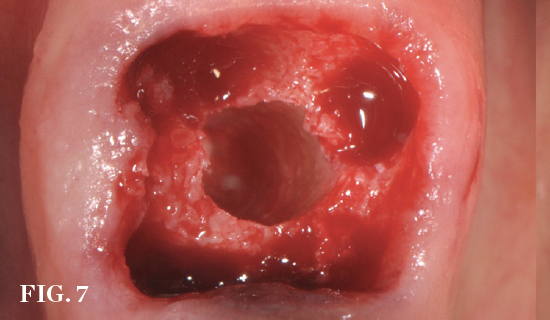

(7.) Restoratively centered guided osteotomy and implant insertion.

Figure 7

(8.) Restoratively centered guided osteotomy and implant insertion.

Figure 8